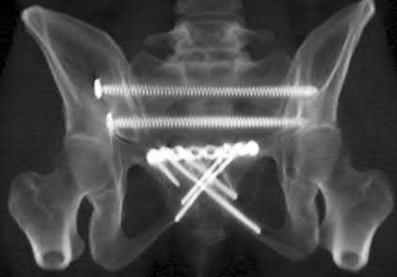

Question 1:

A 35-year-old male is brought to the trauma bay after a severe fall from height. He is hypotensive and tachycardic. An AP pelvis radiograph demonstrates a vertically displaced left hemipelvis with severe disruption of the posterior sacroiliac complex and symphysis pubis. If active arterial hemorrhage is identified on angiography, which vessel is most likely injured in this specific injury pattern?

Options:

- Obturator artery

- Internal pudendal artery

- Superior gluteal artery

- Corona mortis

- Inferior epigastric artery

Correct Answer: Superior gluteal artery

Explanation:

Vertical shear pelvic fractures involve massive disruption of the posterior pelvic ring, including the sacrotuberous and sacrospinous ligaments. The superior gluteal artery exits the pelvis through the greater sciatic notch in close proximity to the sacroiliac joint and is the most commonly injured artery in vertical shear pelvic fractures. In contrast, APC (Anteroposterior Compression) injuries are more typically associated with injuries to the internal pudendal and obturator arteries.